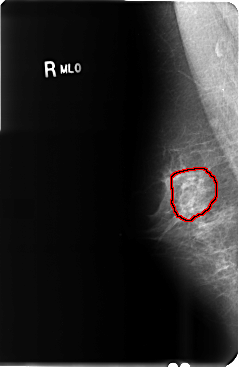

B_3479_1.RIGHT_MLO

FILE: B_3479_1.RIGHT_MLO.OVERLAY

TOTAL_ABNORMALITIES 1

ABNORMALITY 1

LESION_TYPE CALCIFICATION TYPE PUNCTATE DISTRIBUTION SEGMENTAL

ASSESSMENT 4

SUBTLETY 2

PATHOLOGY UNPROVEN

TOTAL_OUTLINES 2

BOUNDARY